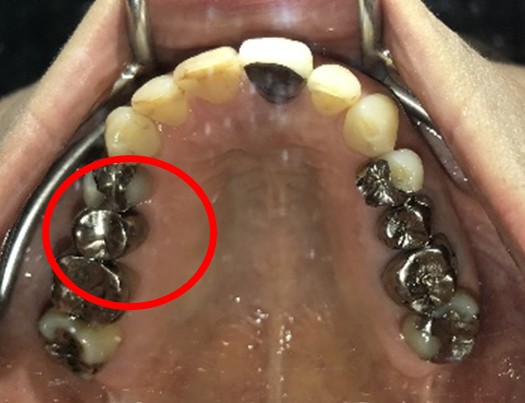

Before

After